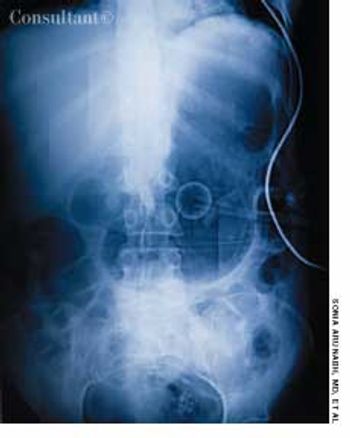

A 70-year-old man was brought from a nursing home to the emergency department with abdominal distention and vomiting of recent onset and a 2-day history of fever and abdominal pain. The patient had chronic obstructive pulmonary disease, type 2 diabetes mellitus, and hypertension. His gastric feeding tube, which had been placed via percutaneous endoscopic gastrostomy, was blocked.